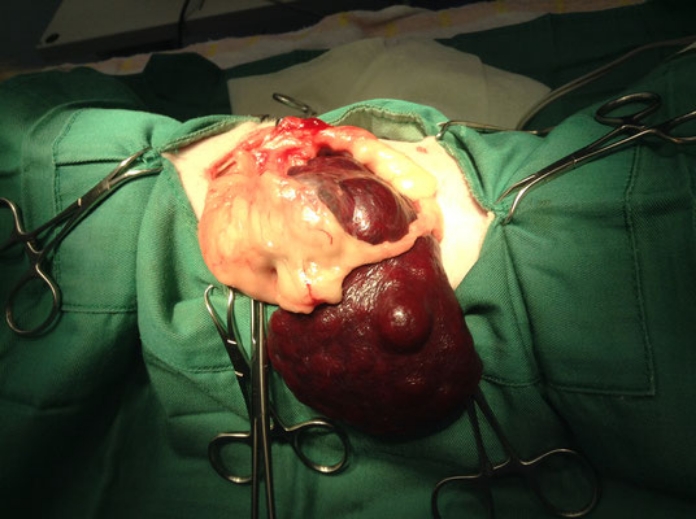

実際の症例

9歳のM.ダックス、チョロちゃん。

下痢を主訴に来院されました。経緯や状態を診て一過性の下痢と思われたので治療を開始しました。

実はこの時身体検査でお腹の中に腫瘤病変を触知したので、下痢が良化したら腫瘤病変の検査を行うことにしました。数日で下痢はよくなったので腫瘤の検査を行いました。

各種検査の結果、脾臓に4cm大の腫瘤が形成されていました。

開腹したところ、破裂を起こし出血している所見はなく、一部癒着を起こしていたものの問題なく摘出することができました。

• 手術画像

• 血腫

病理検査の結果は『血腫』でした。